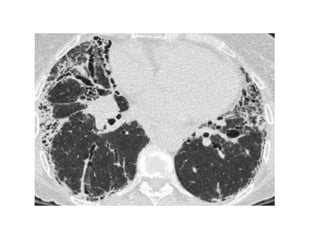

49-year-old woman with persistent and progressive cough, dyspnea, and hypoxemia,

prompting biopsy of her lungs, which revealed chronic desquamative interstitial

pneumonia (DIP) related to extensive cigarette smoking history, CT images through

mid and lower lungs show patchy ground-glass opacities in all lobes of both lungs

with peripheral predilection accompanied by lower lobe bronchial wall thickening, note

small cysts scattered mostly in right lung in regions of ground-glass attenuation,

finding that can occur in DIP